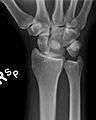

Dislocated lunate

The lunate bone is the most frequently dislocated carpal bone.